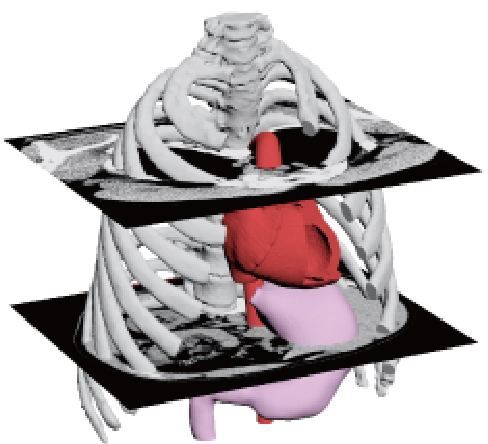

Preoperative simulation

Sternum

A full-scale model of the patient, such as a sternum fixation surgery, can be used for preoperative verification.

In recent years, the evolution and widespread use of dental CT and medical CT has made it possible to obtain data (dentition and skeletal structure) from patients themselves, and by processing the data obtained from CT imaging and outputting it to a 3D printer, preoperative simulations can now be performed on full-scale models. With a full-scale model in hand, the treatment team can share information about the fit, which is not possible on a CAD screen, and formulate an advanced treatment plan.

While most of the models for verification of medical devices used to be made of plaster, in recent years, there has been an increasing demand for soft and transparent models that are closer to the human body. Silicon materials can now reproduce blood vessels, nerves, and cartilage of the nose of the living body, and epoxy light-curing resin materials can be used to make transparent models, so that the inside of the model can be visually checked and the procedure can be confirmed in real time. The bone model can be used not only by medical professionals to confirm procedures and formulate treatment plans through preoperative simulation, but also by medical device manufacturers as a development tool, sales promotion tool, marketing tool, and internal training tool. It can also be used as a development tool for medical device manufacturers, a sales promotion tool, a marketing tool, and an internal training tool.